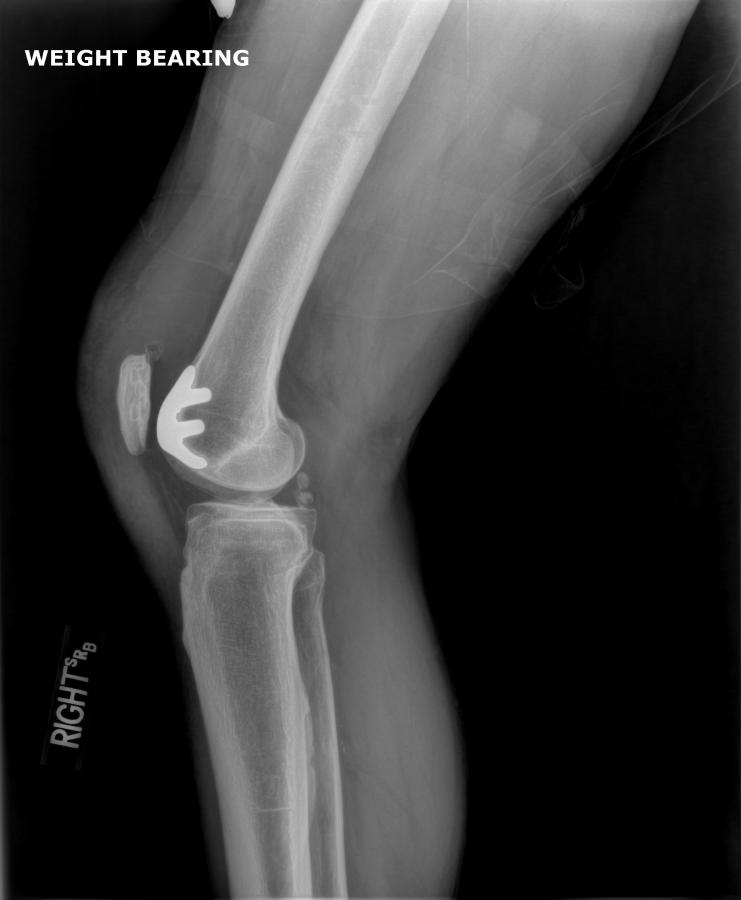

After – Right Knee

After - Right Knee Cap